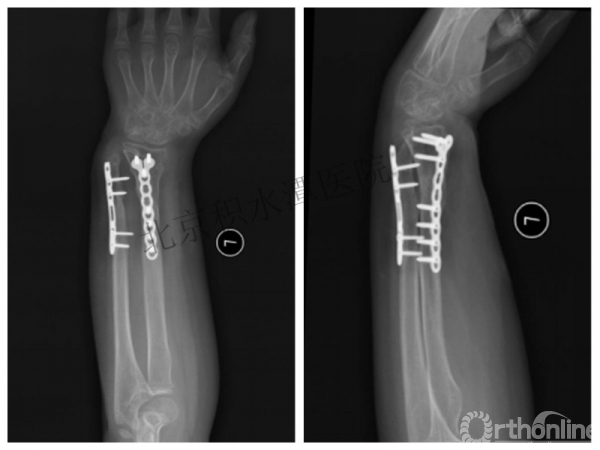

病例分享六

7岁、男孩,桡骨远端骨折

伤后40天—切开复位内固定!

伤后18个月

术后15月,虽然家长满意了,但是他们医生不满意!